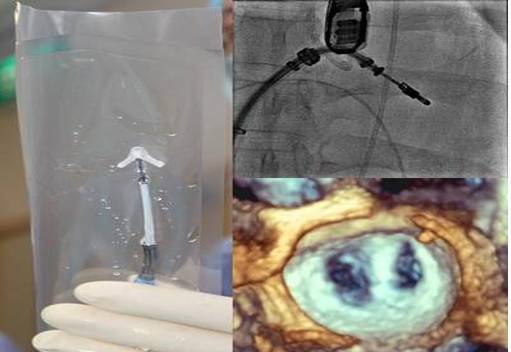

Trans-catheter Mitral Valve Replacement TMVR

◆TS and TA access approaches

◆All self expanding

◆All in the FIM or Phase 1 trials

Acute Human Use, February 2013

[12]